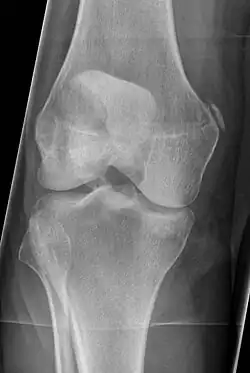

Pellegrini–Stieda syndrome (also called Stieda disease and Köhler–Pellegrini–Stieda disease) is the ossification of the superior part of the medial collateral ligament of the knee. It is a common incidental finding on knee radiographs. It is named for the Italian surgeon A. Pellegrini (b. 1877) and the German surgeon A. Stieda (1869–1945).[1] While the eponym refers to Pellegrini and Stieda, the condition was first discovered by Köhler in 1903, before any namesakes. Pellegrini-Stieda combines the aforementioned radiographic findings and concomitant medial knee joint pain or restricted range of motion.[2]

Diagnosis is typically made on radiographs demonstrating the Pellegrini-Stieda syndrome sign accompanied by pain or restriction of range-of-motion of the knee joint.[2] Pellegrini-Stieda syndrome sign is typically described by a longitudinally linear opacity, which is a process that is describes characteristic of calcification in the soft tissue located medial to the medial femoral condyle.[2] This calcification seen on imaging represents the ossification of the medial collateral ligament, which typically does not develop until approximately three weeks after the initial injury.[2]It is important to note to distinguish this radiographic finding from that of a medial femoral condyle avulsion fracture, which is an injury in which a pulling force of a tendon or ligament fractures away a piece of the bone from its attachment site.[2]